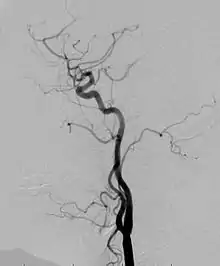

Angiogram

Angiogram: an angiogram can also be ordered to get a detailed look at the blood vessels in the affected or overgrown limb. In this test a physician injects a dye into the blood vessels that will help see how the blood vessels are malformed.[22]